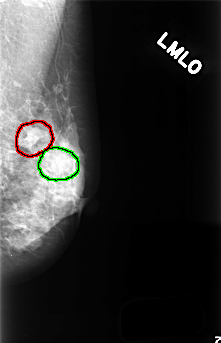

FILE: C_0418_1.LEFT_MLO.OVERLAY

TOTAL_ABNORMALITIES 2

ABNORMALITY 1

LESION_TYPE MASS SHAPE LOBULATED MARGINS OBSCURED

ASSESSMENT 3

SUBTLETY 5

PATHOLOGY BENIGN

TOTAL_OUTLINES 1

BOUNDARY

ABNORMALITY 2

LESION_TYPE MASS SHAPE OVAL MARGINS CIRCUMSCRIBED

SUBTLETY 3